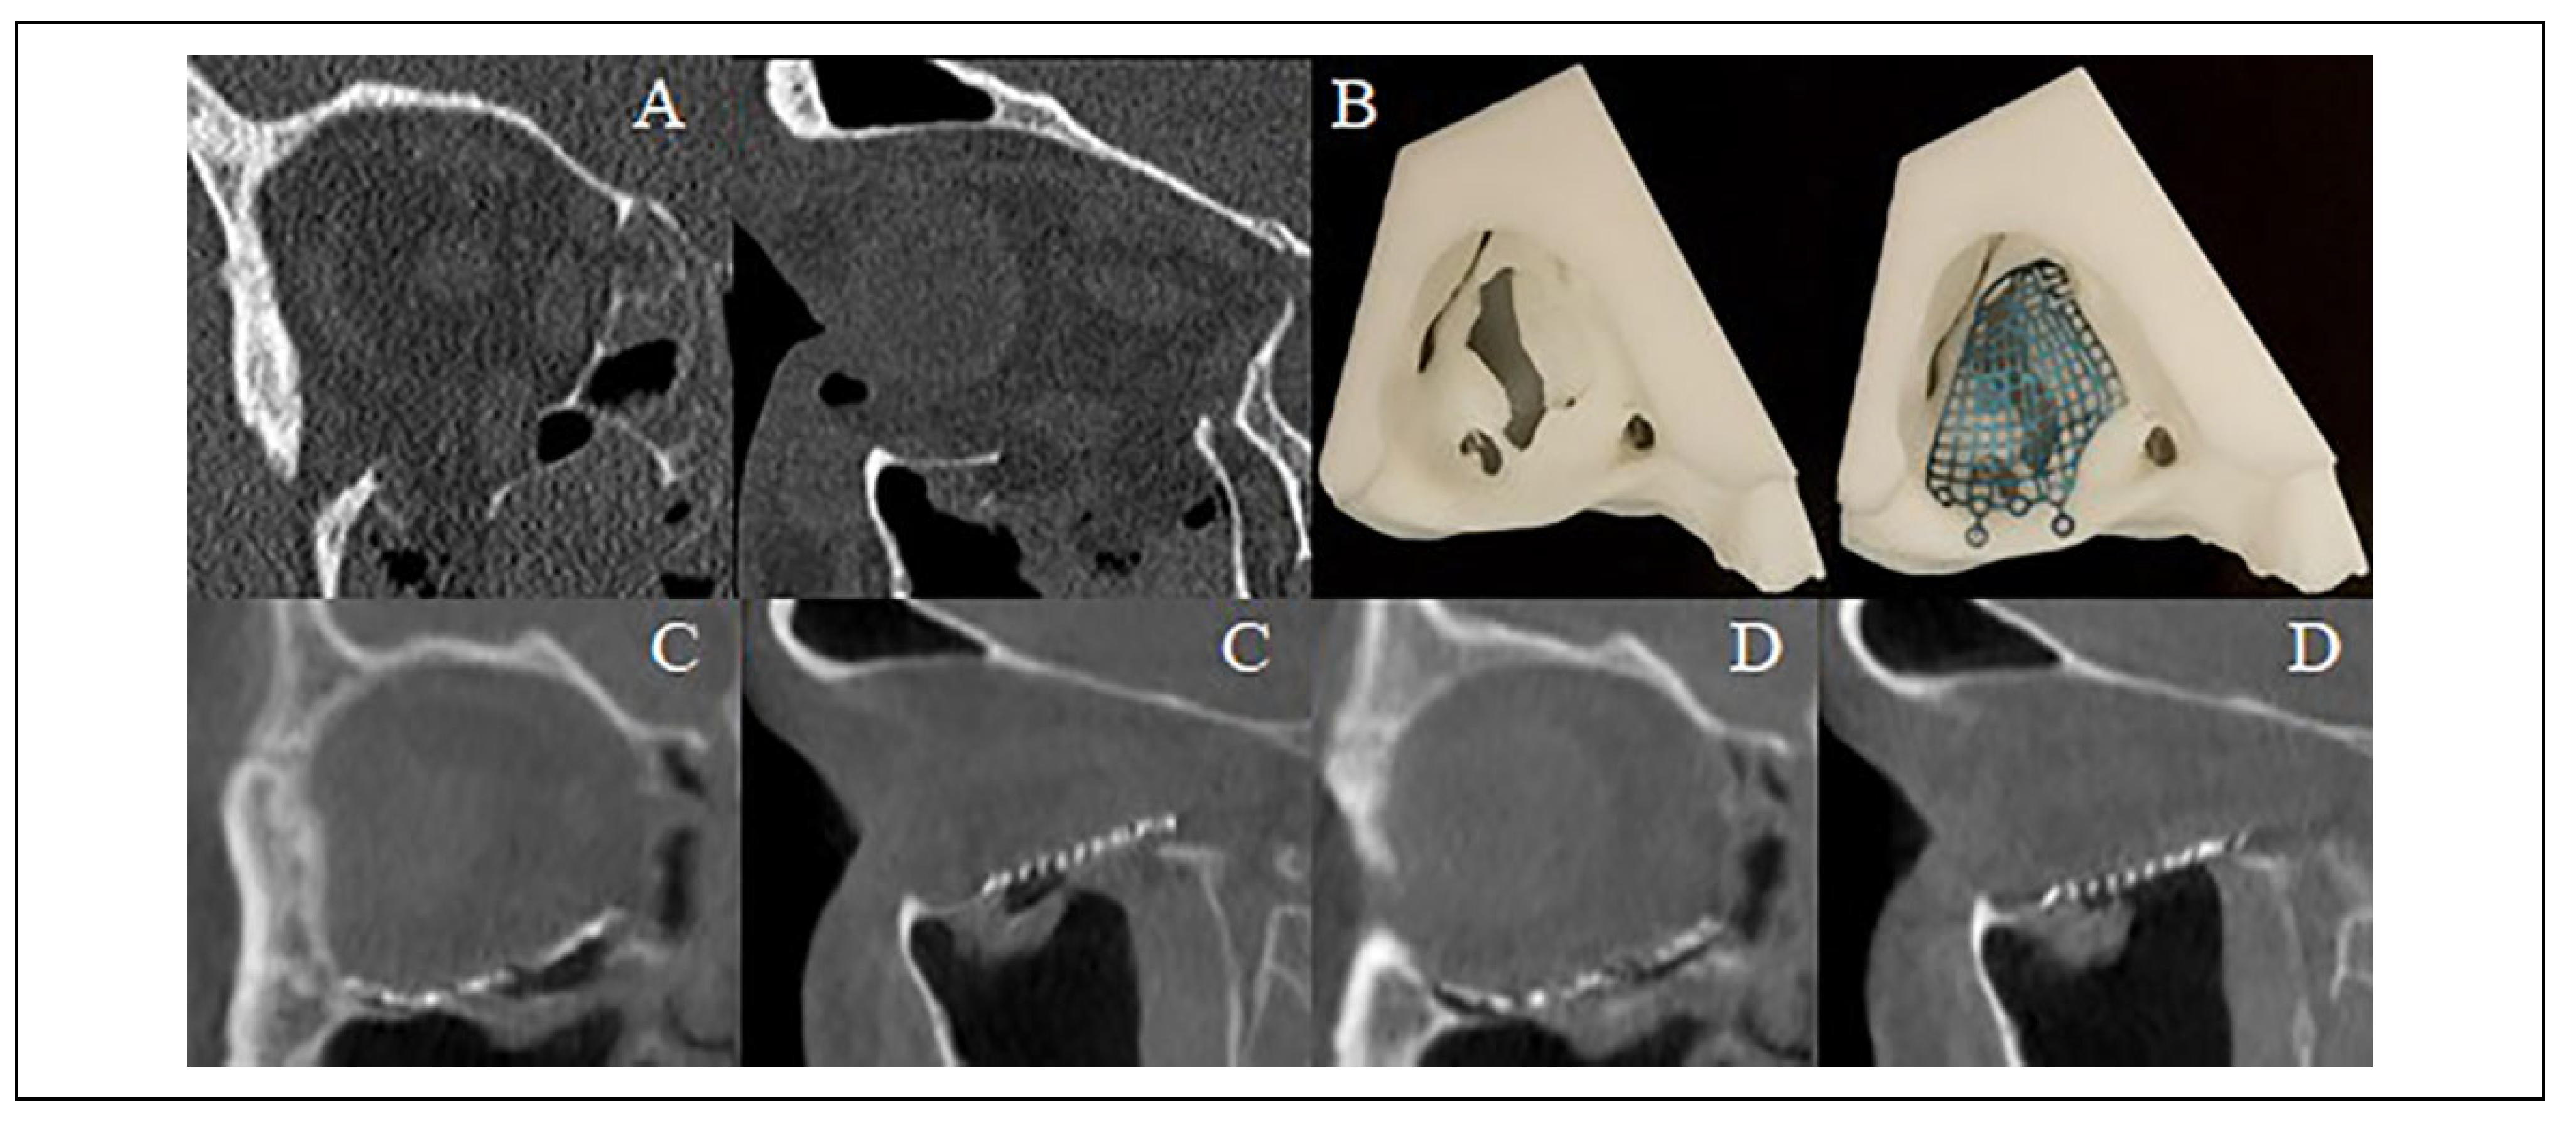

Figure 5.

(A) Isolated right orbital floor fracture with herniation of the inferior rectus muscle into the fracture defect. (B) 3D printed rapid prototype biomodel and pre-bent Leibinger reconstruction plate prior to sterilization. (C) First O-arm “spin” demonstrating plate malposition within the orbit and (D) second O-arm “spin” demonstrating favorable reconstruction after adjusting plate position.